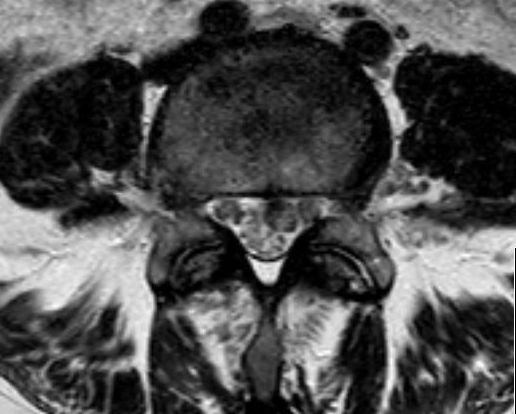

Rückenmarks-Metastasen

48-jährige Patientin mit einem kleinzelligen, neuroendokrinen Bronchialkarzinom. Taubheit der Füße, Kraftminderung und Hypästhesie beider Beine.

RM-Metastasen

Rückenmarks-Metastasen Rückenmarks-Metastasen Rückenmarks-Metastasen